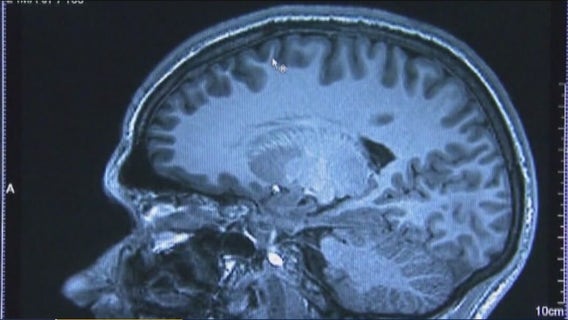

A Texas A&M student from Houston is happier than ever to head back to class next week. He's getting a second chance at life, after spending the last seven months recovering from a catastrophic brain injury.

A Houston-area man is sharing his journey with a type of dementia, that is often misdiagnosed. Researchers at UTHealth Houston tell us, for the first time, they could be on the brink of a successful treatment to reverse the disease.